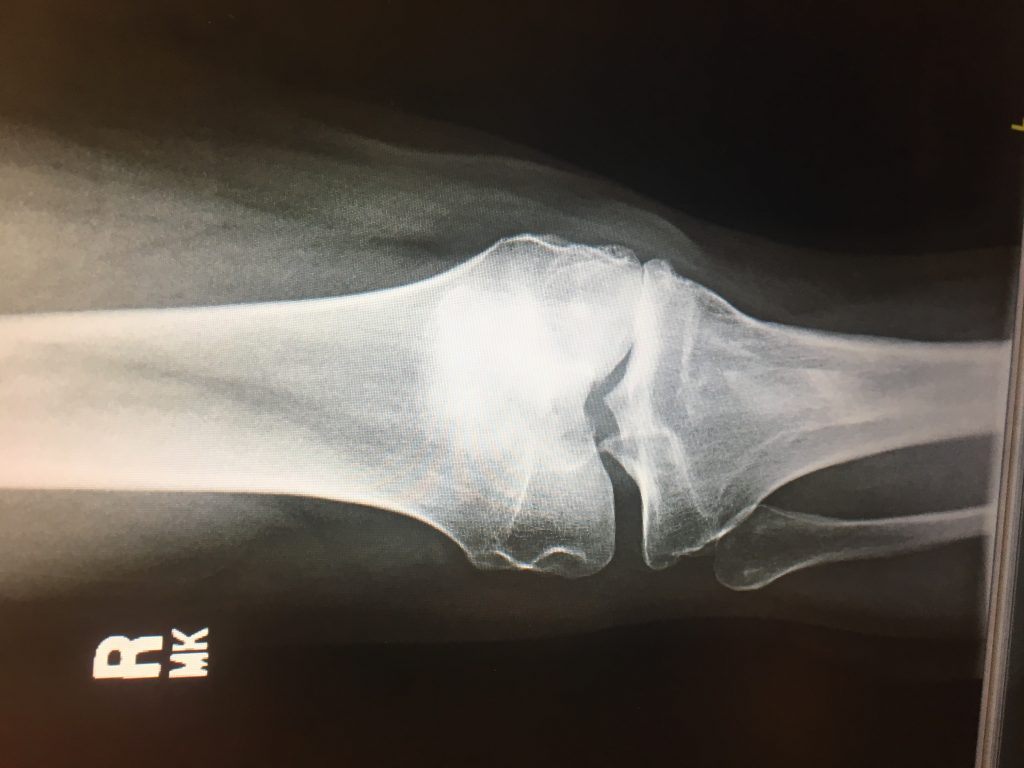

I was living with bone on bone pain with levels reaching 8-10 in my right knee for 2 years. I did PT and various injections to no avail. The recommendations from local providers was a full knee replacement. I researched the latest knee reconstruction techniques and learned about partial replacements on the HSS website. Based on the patient criteria described I felt I was a candidate for this type surgery. Then I discovered that HSS was ranked #1 by US News and World Report as the best hospital for orthopedic surgery for 8 years in a row. That was in May of 2018 and now after the latest rankings it is 9 years in a row! Well done HSS. Once I found my hospital of choice I started researching doctors and discovered Dr. Nawabi for partial knee replacements. His health grades were outstanding and patient testimonials compelled me to make an appointment. After my thorough consultation I was convinced he would be my surgeon. He is easy to talk to, communicates in language you can understand, is patient, and extremely credible. I had total trust he would do the best surgery possible for my knee.

Instead of replacing my whole knee, Dr. Nawabi was able to save 2/3's of my knee. 6 months after surgery I have very little pain and enjoy an active lifestyle. I have provided pictures of my bone on bone knee prior to surgery and the partial knee replacement 6 months after surgery. I even hiked in the Rocky Mountain National Park just 10 weeks after surgery.